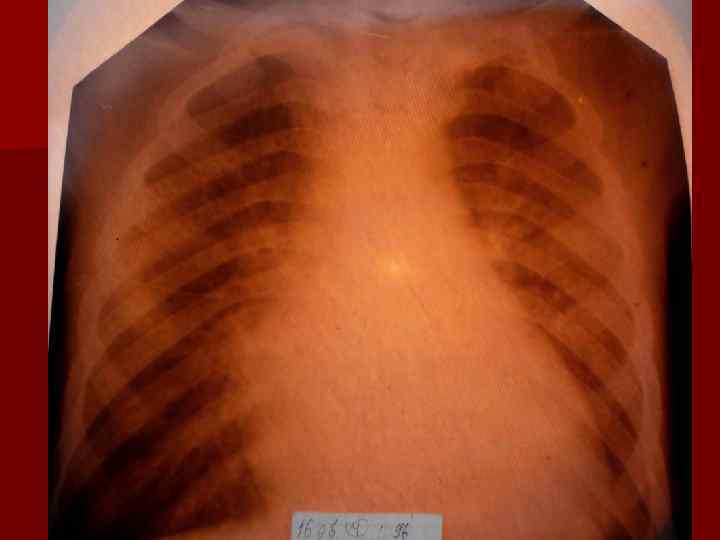

Долевая пневмония характеризуется лобарным пневмоническим инфильтратом. Крупозная ( пневмококковая) пневмония диагностируется прежде всего по клиническим данным. Крупозная пневмония сохраняет свою типичную картину пневмококковой пневмонии: острое начало с характерными клиническими данными, циклическое течение, несклонность к деструкции, гомогенной и лобарной инфильтративной тенью при рентгенологическом исследовании. Вместе с тем, широкое использование антибиотиков способствовало значительному снижению числа крупозных пневмоний у детей. Интерстициальная – редкая форма пневмоний, при которой оказывается поражен прежде всего интерстиций. Как правило, интерстициальная пневмония обусловлена вирусами, пневмоцистами, внутриклеточными микроорганизмами и грибами.

Морфологическую форму пневмонии определяют по клинико – рентгенологическим данным: выделяют очаговую, очагово – сливную, долевую ( крупозную), сегментарную и интерстициальную пневмонии. Очаговая – наиболее распространенная форма. Пневмонические очаги чаще бывают размером 1 см и более. Очагово – сливная – инфильтративные изменения в нескольких сегментах или во всей доле легкого, на фоне которых могут быть видны более плотные участки инфильтрации и/или полости деструкции. Сегментарная – в процесс вовлекается весь сегмент, который, как правило, находится в состоянии гиповентиляции, ателектаза. Морфологическая картина воспаления при очаговых и сегментарных пневмониях связана с первичным инфекционным воспалением в бронхах, что дает основание отнести эти варианты поражения легочной ткани к бронхопневмониям, нередко сопровождающихся бронхообструктивным или бронхообтурационным синдромами. В настоящее время данный тип пневмоний у детей встречается наиболее часто.